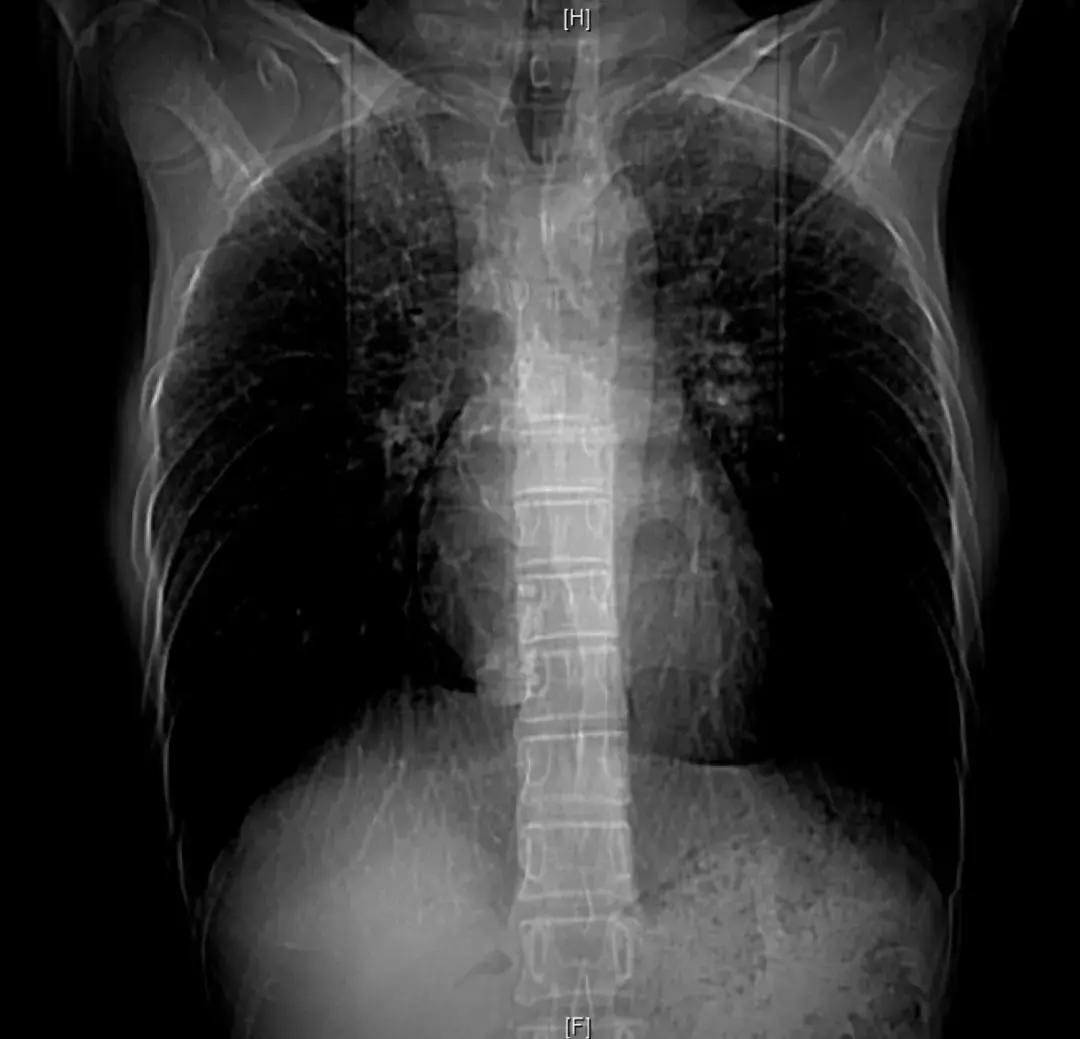

2014-02-21(入院第2天)胸部CT:

发现与2013-10-12胸部CT相似,主要还是以双上肺和胸膜下为主的网格状影,其次右下肺有片状影,可看到充气支气管征。